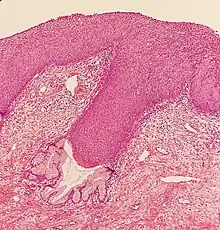

CIN is classified in grades:[17]

| Histology grade | Corresponding cytology | Description | Image |

|---|---|---|---|

| CIN 1 (Grade I) | Low-grade squamous intraepithelial lesion (LSIL) |

|

![]() |

| CIN 2/3 | High-grade squamous intraepithelial lesion (HSIL) |

| CIN 2 (Grade II) |

![]() | |

| CIN 3 (Grade III) |